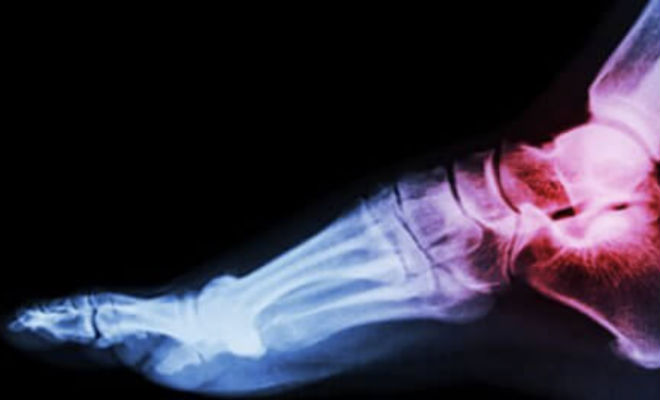

К таким относится чрезвычайно редкая мутация гена LRP5. Такие люди настоящие везунчики, ведь эта мутация делает их кости невероятно крепкими. Да еще и кожа у них стареет медленно, что дает им молодость до самой старости.